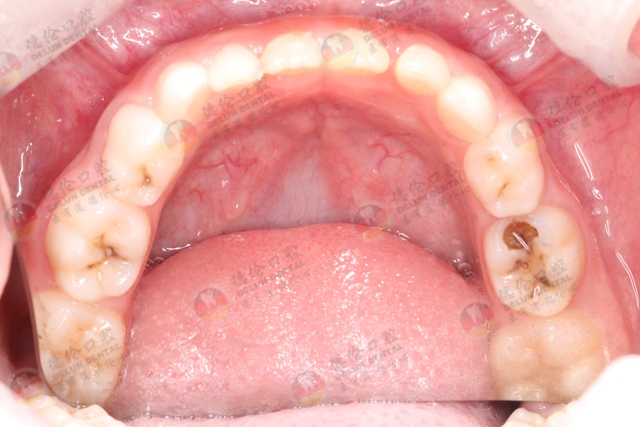

检查孩子的萌出状况、形态、数目、颜色、填充等,比如说有没有龋齿、乳牙早失、乳牙滞留,多生牙、先天缺牙等,早期发现并及时处理,能够减少对恒牙萌出造成不良影响。

02、检查牙齿的情况